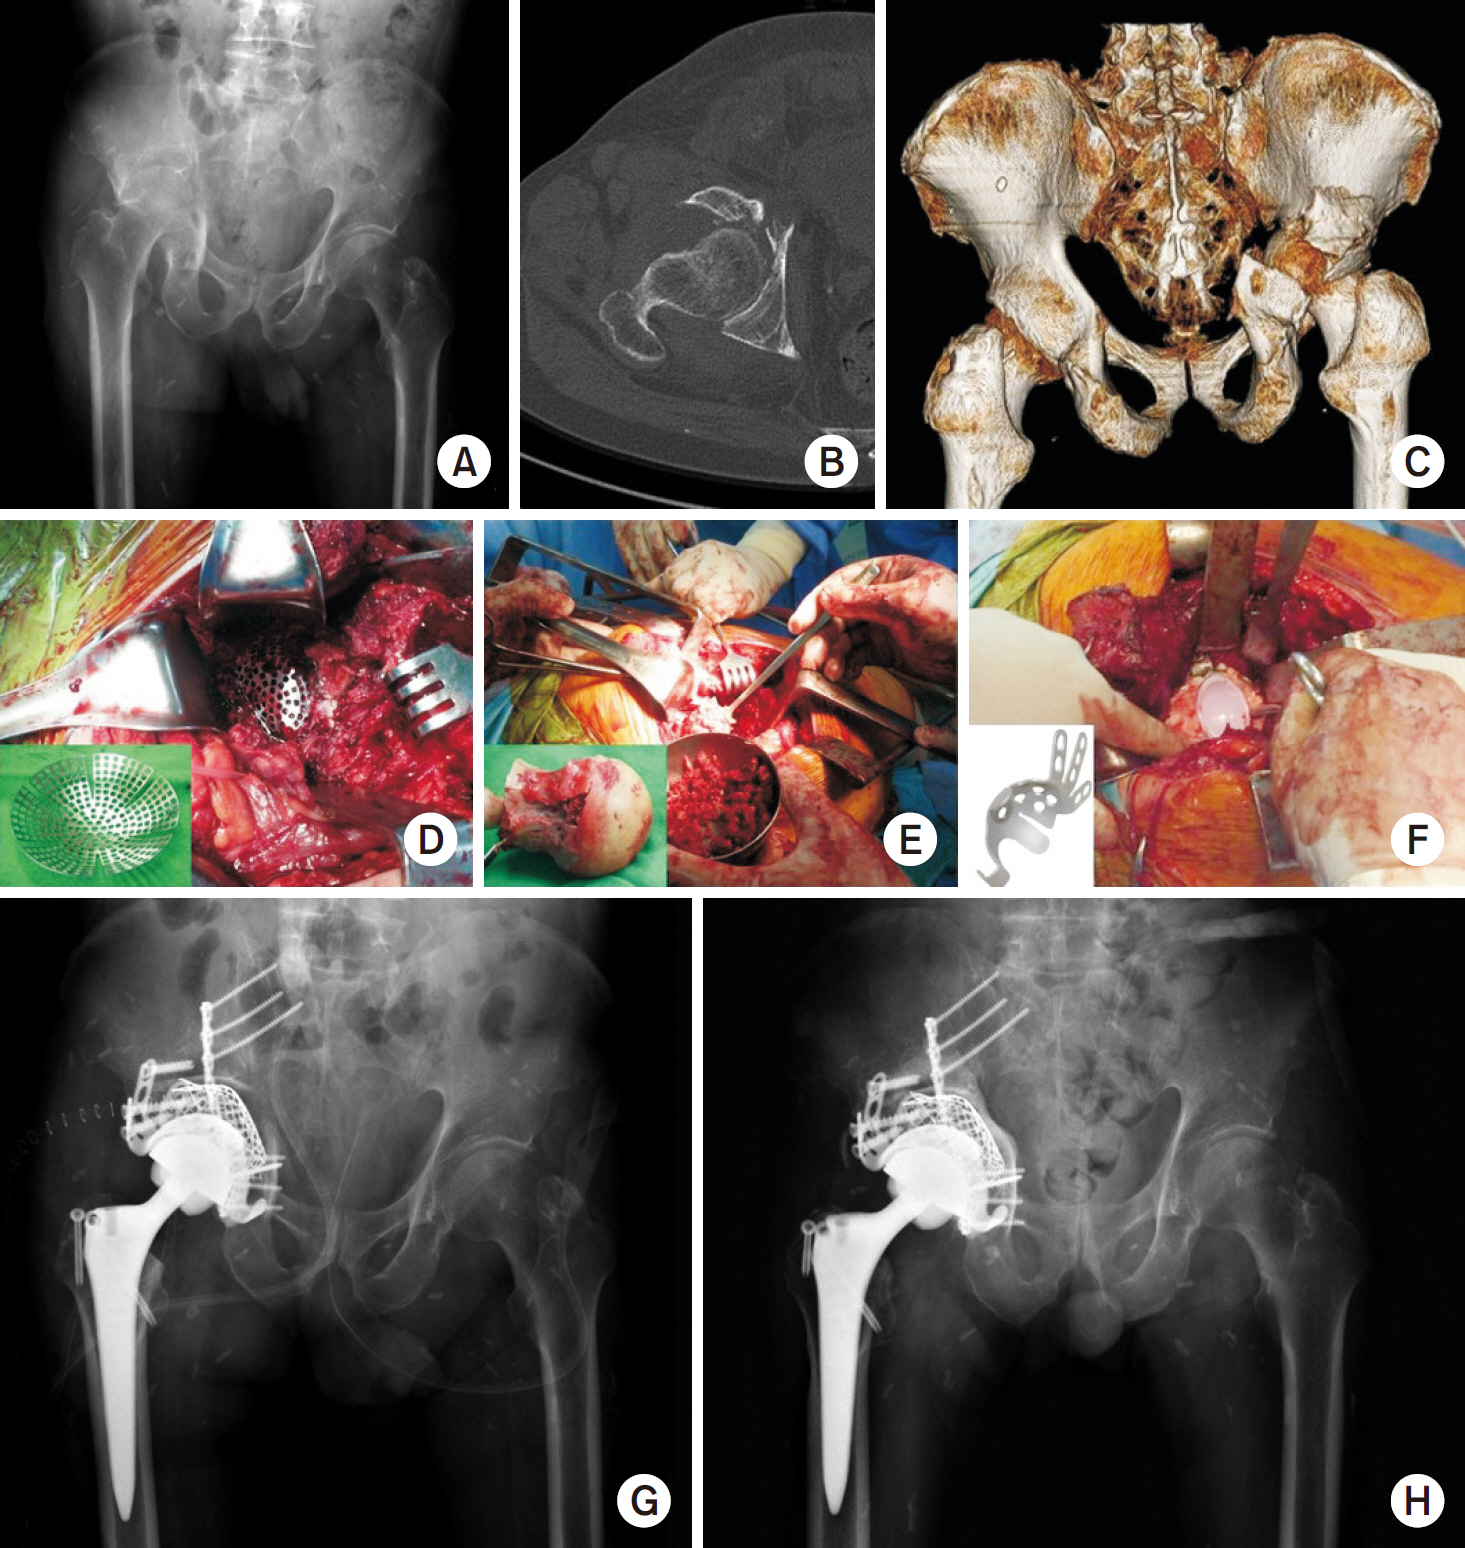

Fig. 3.

(A) Preoperative anteroposterior radiograph of a 50-year-old male showed a transverse fracture with a posterior wall fracture of the acetabulum. (B, C) The three-dimensional reconstruction images showed the impaction of acetabulum and comminuted fragments. (D) Postoperative anteroposterior radiograph after internal fixation through the Kocher–Langenbeck approach. (E) Seven-month postoperative radiographs showed post-traumatic osteoarthritis on the left hip joint. (F) Intraoperatively, the resected femoral head showed denuded and destroyed articular cartilage. (G) Postoperative anteroposterior radiograph after total hip arthroplasty. (H) Five-year postoperative radiographs showed a stable total hip component with no complaint.